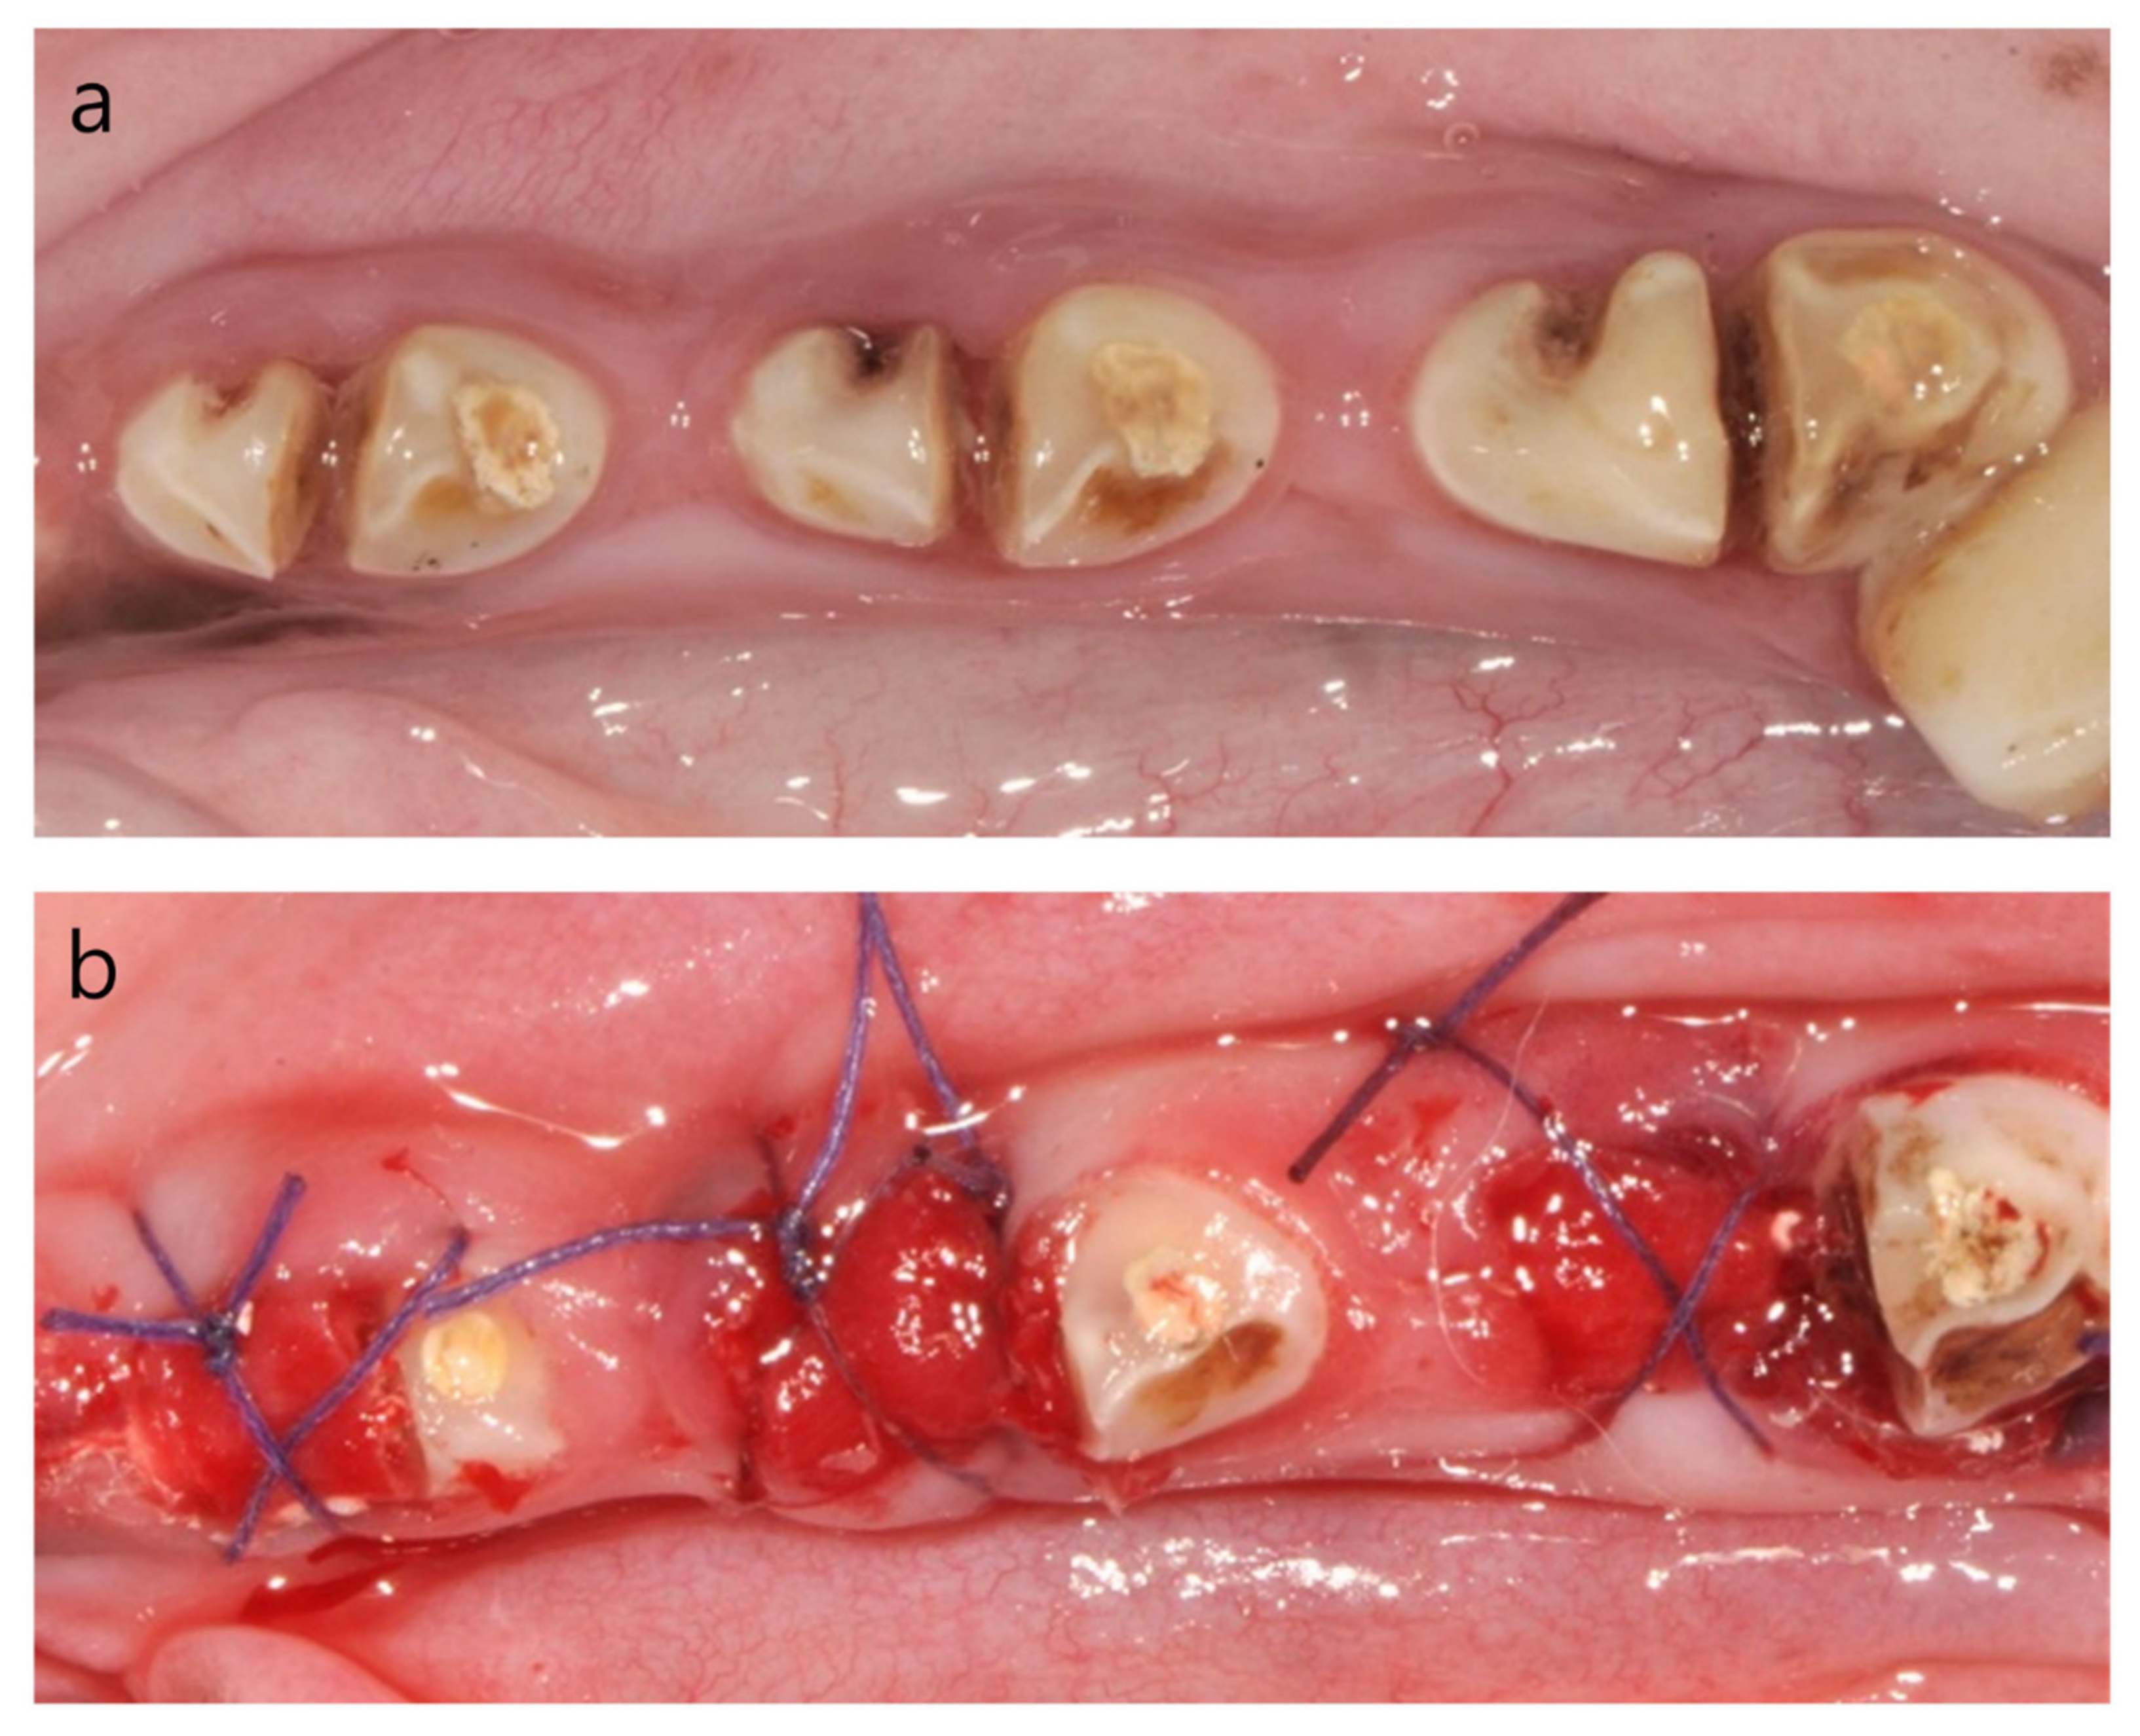

General anesthesia was induced by intravenous injection of Zoletil (250 mg tiletamine hydrochloride in powder and 250 mg zolazepam hydrochloride in powder is mixed with 5 mL of solvent; 0.1 mg/kg; Virbac, Carros, France), xylazine (2.3 mg/kg; Rompun, Bayer Korea, Ansan, Korea), and atropine sulfate (0.05 mg/kg; Jeil, Daegu, Korea). Thereafter, local anesthesia was induced by injecting 1:100,000 epinephrine-containing lidocaine (Huons, Sungnam, Korea). Intracrevicular incisions were made in the mandibular premolar area, and the flaps were elevated (Figure 2a,d). The mandibular second, third and fourth premolars (P2, P3, and P4) were hemi-sectioned by using a diamond burr (Figure 2c). The pulp of the distal root was extracted with a 25 mm K-file (#15 and #20, MANI, Inc., Utsunomiya, Tochigi, Japan), and obturated with a gutta-percha master cone using cold condensation with accessory cones of AH Plus (Dentsply, DeTrey GmbH, Konstanz, Germany). After the root canal treatment, the distal root was sealed with intermediate restorative material (IRM; Dentsply Sirona, Milford, DE, USA; Figure 2c). A dehiscence defect, measuring 3 mm in width and 4 mm in height, was created at the mesial root, and a groove on the buccal area from the top of the teeth to the bottom of the defect was also made, thereby exposing the dental pulp (Figure 2d,e). The surgical site was closed with 4/0 Vicryl (Figure 2f). Suture removal was done 1 week after the surgery.

Figure 2. Clinical photographs of the induction of the dehiscence defect with chronic pathology. (a) Preoperatively, (b) flap elevation, (c) hemi-section and distal root canal treatment, (d) creation of a dehiscence defect on the buccal side of the mesial root, (e) a vertical notch on the buccal side with exposure of the pulp of the mesial root, and (f) flap suture.